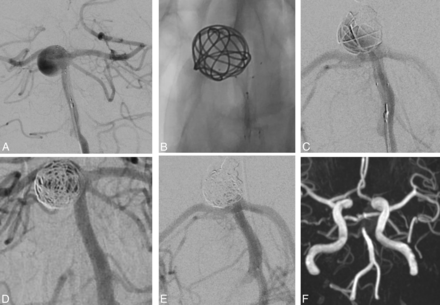

A 60-year-old woman (Fig 4, patient 14) presented with an unruptured basilar tip aneurysm. Angiography showed a large basilar tip aneurysm with a 4-mm-wide neck. Endovascular treatment was performed by using a PulseRider. The final angiogram showed complete aneurysm occlusion, and MRA at 1 day showed complete aneurysm occlusion.

An unruptured basilar tip aneurysm in a 60-year-old man (case 3). A, Subtracted angiography shows a large basilar tip aneurysm with a 4-mm-wide neck. B–D, Endovascular treatment was performed by using a PulseRider device. E, Subtracted angiography at the end of the procedure shows complete aneurysm occlusion. F, MRA at 1 day shows complete occlusion.